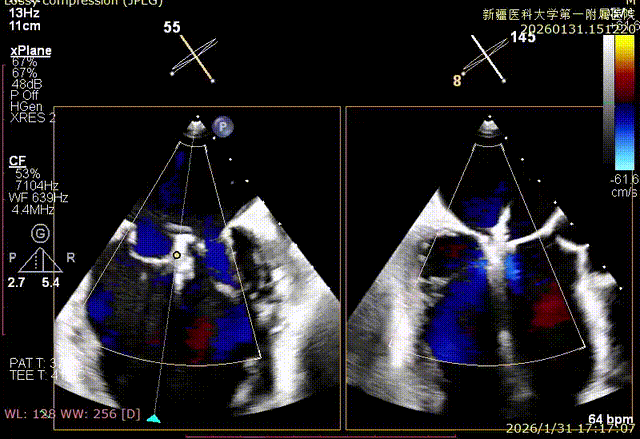

XPLAN切面2区后叶栓系

XPLAN切面中重度反流

XPLAN后叶严重栓系

Bicom切面中重度反流